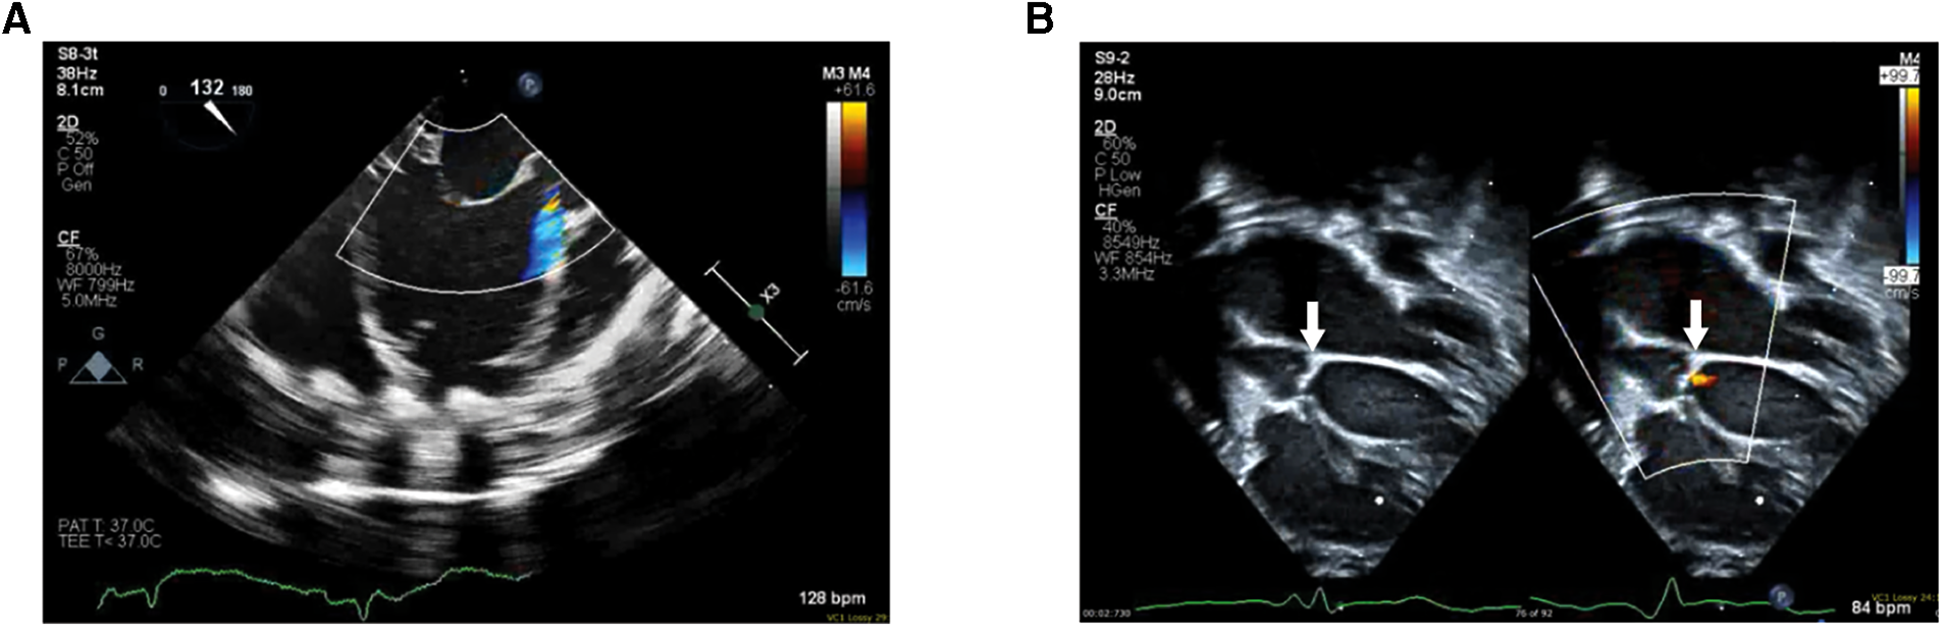

The patient was a 9-day-old, 2.7 kg female born at full term who presented with tachypnea, retractions, and cyanosis. An echocardiogram in clinic was notable for poor left ventricle function and she was immediately admitted to the intensive care unit. She was intubated for respiratory distress and started on empiric antibiotics. She was then transferred to our center for further care. Echocardiogram upon transfer demonstrated severely reduced left ventricle systolic function, mildly depressed right ventricle systolic function, and no semilunar or atrioventricular valve insufficiency. She was then evaluated and listed for heart transplantation. Five days after admission, the patient developed hemodynamic instability despite increased inotrope infusions and thus underwent urgent cannulation for venoarterial extracorporeal membrane oxygenation followed by balloon atrial septostomy for additional decompression of the left heart. She was then transitioned to a Berlin Heart EXCOR VAD two weeks later. Echocardiogram prior to VAD implantation demonstrated the presence of a nonrestrictive atrial septal defect with left to right shunting, severely depressed left ventricle systolic function, left ventricle dilation, mild mitral insufficiency, moderate and continuous AI (Figure 2A), mildly reduced right ventricle function, trivial tricuspid insufficiency, and mild to moderate mitral insufficiency. Given the degree of aortic insufficiency, an aortic valve repair was also undertaken in addition to the atrial septal defect closure and VAD placement. Via median sternotomy, cardiopulmonary bypass was accomplished with ascending aorta and bicaval cannulation. A 5 mm inflow cannula was inserted through the left ventricle apex. Cardioplegic arrest was then accomplished by administering Del Nido solution into the aortic root. A longitudinal aortotomy was then performed on the anterior ascending aorta and extended into the noncoronary sinus to expose the aortic valve. The leaflets were very thin and were noted not to coapt centrally. Because the leaflets were too fragile to hold a central coaptation stitch, we elected to close the ventriculoaortic junction with a patch of bovine pericardium. The leaflets were excised and the bovine pericardial patch was sewn to the annulus with a continuous 7-0 polypropylene suture. The aortotomy in the noncoronary sinus region was then closed, and a slightly beveled 8 mm vascular graft was anastomosed to the anterior aortotomy. The vascular graft was then connected to a 5 mm Berlin outflow cannula that had been previously tunneled through the body wall. The atrial septal defect was closed with a Gore-Tex patch. The VAD cannulae were connected to a 10 ml Berlin Heart Excor blood pump. The heart and VAD were deaired and the aortic cross-clamp was removed. The patient was weaned off cardiopulmonary bypass with the level of VAD support titrated while using echocardiogram to determine ventricular septal position and the degree of tricuspid regurgitation. Total cardiopulmonary bypass time was 169 min, with an aortic cross-clamp of 75 min. Transesophageal and epicardial echocardiogram demonstrated a trivial ventriculoaortic patch margin leak (Figure 2B), no residual atrial level shunting, good right ventricle function, and laminar flow into the inflow cannula. The patient recovered uneventfully and then underwent orthotopic heart transplantation two months after VAD implantation. The patient required the placement of a gastric tube for feeding difficulties and was discharged 6 weeks after heart transplantation.

Figure 2

(A) Pre-VAD implantation echocardiogram with color doppler mapping demonstrating significant AI. (B) Post-VAD implantation 2D echocardiogram (left) with color-doppler comparison (right) demonstrating the patch placed at the ventriculoaortic junction (white arrows) and trivial patch margin leak.